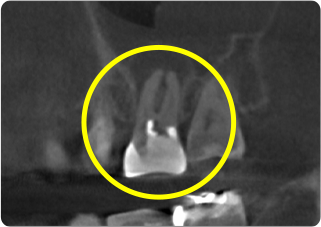

精密根管治療④

術前

術後

| 主訴 | 奥歯で噛むと痛い |

|---|---|

| 治療期間/回数 | 1ヵ月、3回 |

| 価格(税込) | 88,000円(税込) |

| リスク・副作用 | 病変再発、歯根破折の可能性 |

| ポイント | う蝕検知液を用い、むし歯の取り残しが無いようにし、ラバーダム防湿を行い、無菌的に根管治療を行った。根管充填材は、殺菌作用の強い保険適応外のMTAセメントを使用した。 |